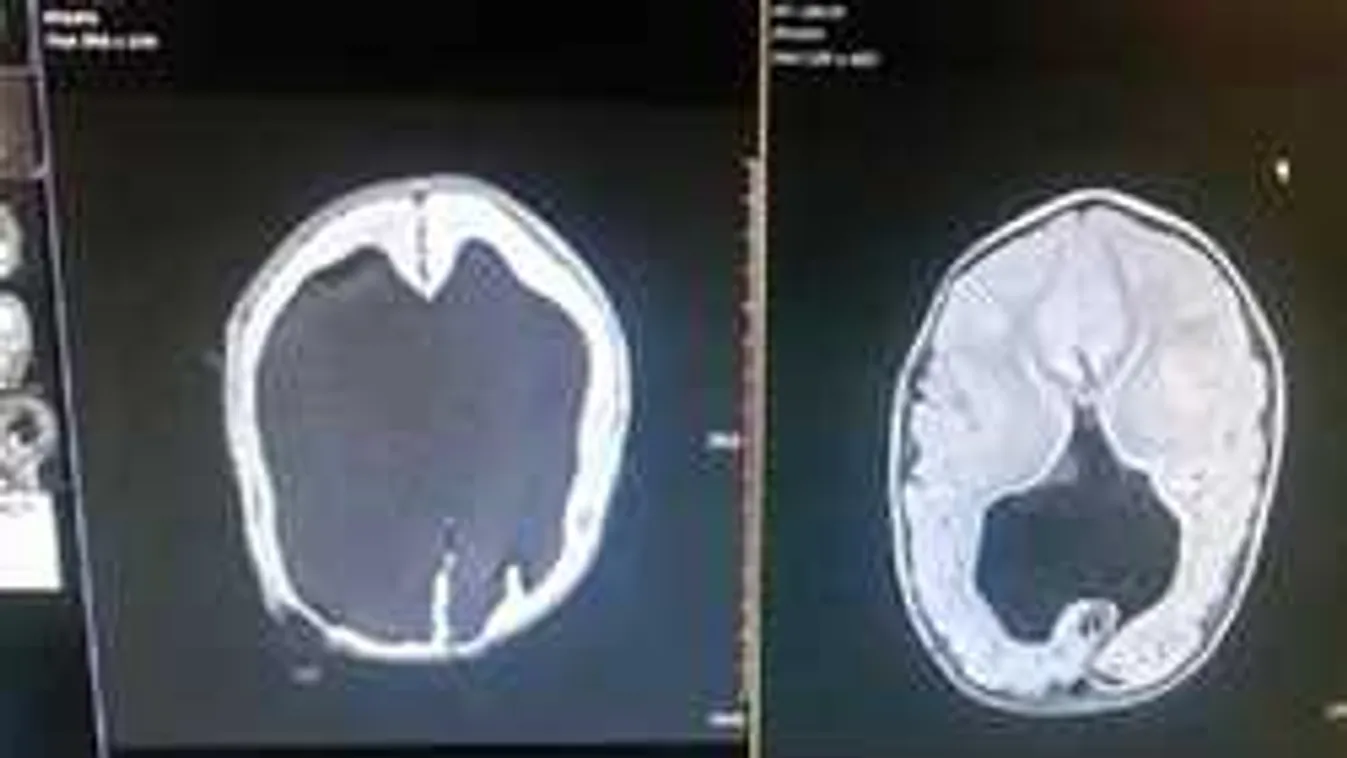

Mindössze agya két százaléka működött Noah Fahlnak, amikor megszületett. Az angliai Cumbriában élő Shellyt orvosai a terhessége alatt végig győzködték, hogy ne akarja megszülni kisfiát. Noah koponyája ugyanis összetört az anyaméhben, s feje folyadékkal lett tele.

Vagyis a gyerek vízfejűségben szenvedett. A vízfejűség komoly fogyatékosság, így érthető, hogy az orvosok próbálták lebeszélni Shellyt a szülésről.